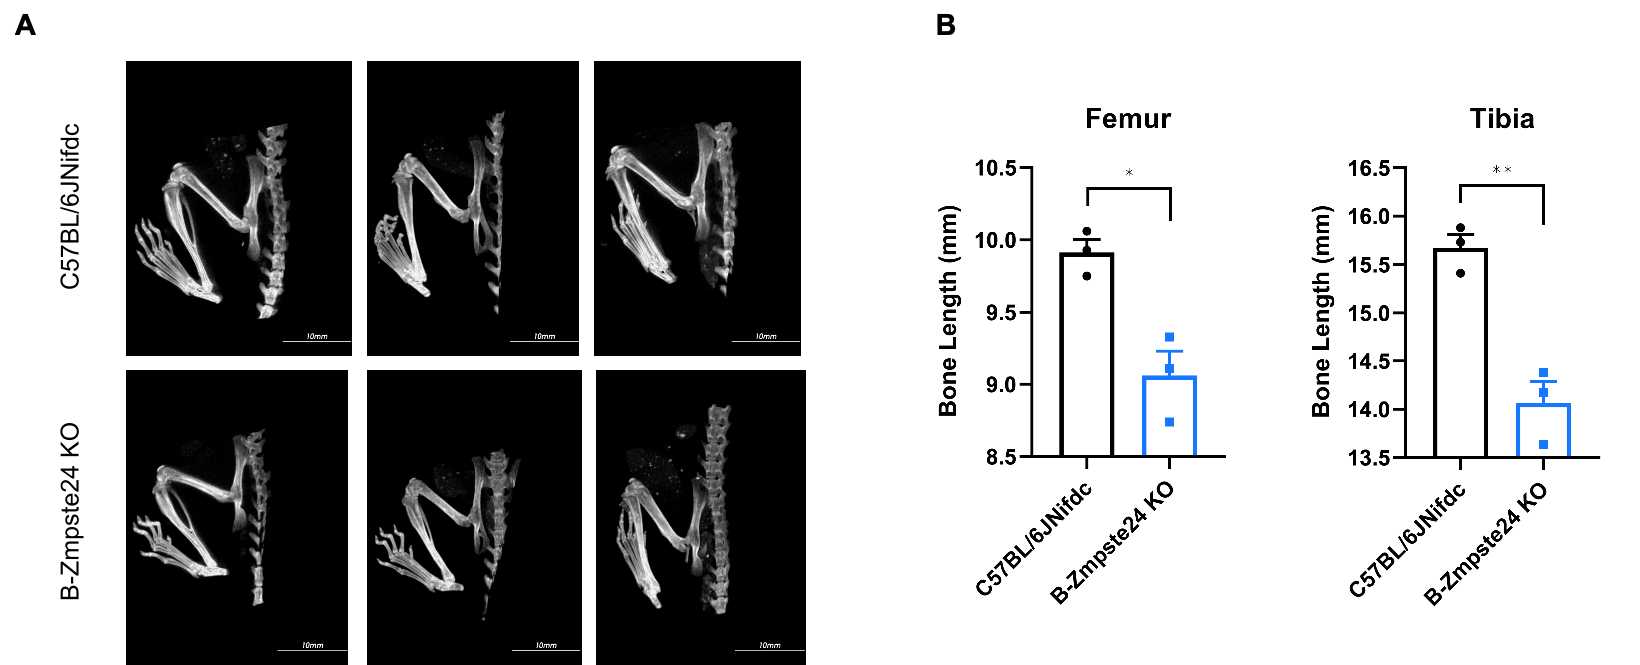

Micro-CT analysis of femur and tibia length in homozygous B-Zmpste24 KO mice. (A) Representative micro-CT images of femur and tibia from wild-type C57BL/6JNifdc mice (n=3, male, 6-week-old) and homozygous B-Zmpste24 KO mice (n=3, male, 6-week-old). (B) Quantitative comparison of femur and tibia length. In the homozygous B-Zmpste24 KO mice, the lengths of the femur and tibia were shortened. Data are presented as mean ± SEM. *P < 0.05, **P < 0.01, ***P < 0.001. Scale bar = 10 mm.